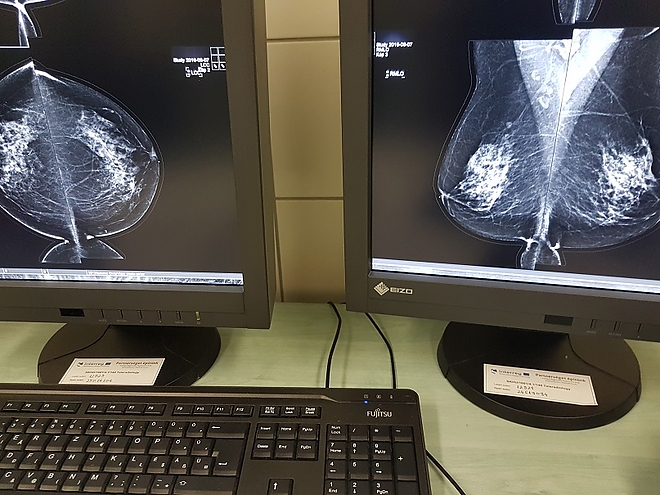

A fejlesztés részeként Miskolcon a már meglévő rendszer fejlesztéséhez, míg Királyhelemcen a rendszer bevezetéséhez szükséges informatikai hardver, valamint szoftver elemeket szereztek be. A PACS egy olyan technológia, amely képes kezelni, archiválni, megjeleníteni és megosztani a képi dokumentációt, például a röntgen, a mágneses rezonancia és a CT képeket.

Kostyál László, a Borsod-Abaúj-Zemplén Megyei Központi Kórház és Egyetemi Oktatókórház Képalkotó Diagnosztikai Centrumának osztályvezető főorvosa hangsúlyozta: a szlovák részről nagyobb beruházást jelentett a projekt, „ugyanis ők egy új gépet, egy teljesen új technikát kaptak”, a Borsod megyei egészségügyi intézményben a már meglévő technikának a modernizálása és a felgyorsítása volt a cél, ennek részeként készült 13 új leletező állomás az osztályra.

– A fejlesztésnek köszönhetően a képek gyorsan „lejönnek”, azonnal megtekinthetők. Nagyon fontos lenne, hogy a szlovák munkatársak itt, Miskolcon is gyakorlatot, tudásanyagot szerezzenek, hiszen a megyei kórházban naponta mintegy 130 CT vizsgálat történik, ott pedig 10-15. Eddig mintegy 60-80 leletanyag érkezett Királyhelmecről, itt nem is a mennyiség, hanem a képek minősége, felbontása volt a fontos, hogy kiváló, tökéletesen kiértékelhető legyen valamennyi – tette hozzá.